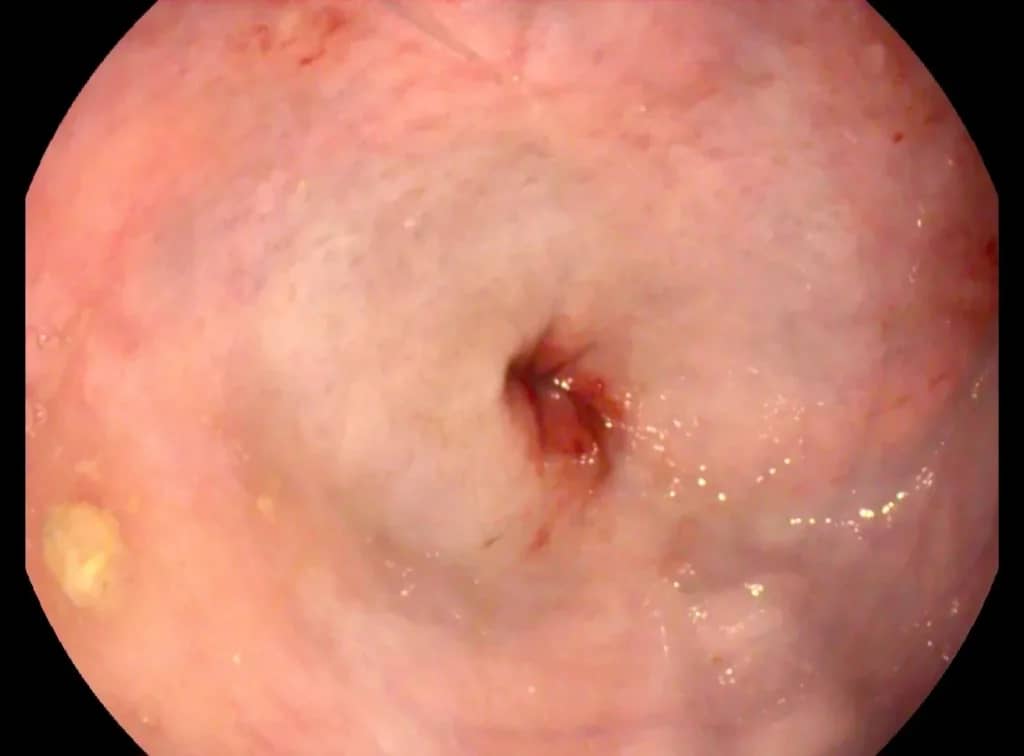

Важно: Мегаэзофагус вызывает именно срыгивание. Если вы видите, что питомец срыгивает непереваренной пищей — это повод для срочной диагностики